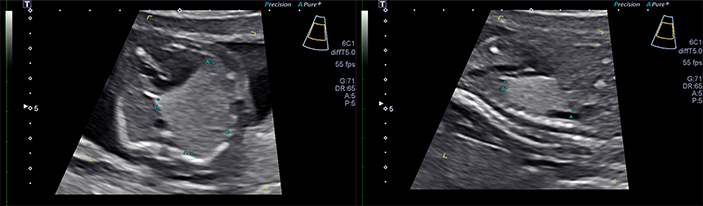

- Type I CPAMs account for 50% of cases and have relatively few large cysts, ranging in size from 3 to 10 cm. Figure 1 shows the fetus with a left upper lobe type I congenital pulmonary airway malformation that has a large unilocular cyst which is shifting the heart and mediastinum to the left and compressing the left lower lobe.

- Type II CPAMs account for 40% of cases and have numerous cysts of smaller size, usually less than 1 cm. Type II CPAMs are associated with multiple congenital anomalies. Figure 2 shows the fetus with a type II CPAM in which the cysts are smaller than in type I.

- Type III CPAMs are usually large homogeneous, solid-appearing masses, which can grow to large sizes in utero and result in nonimmune hydrops. Figure 3 shows a type III CPAM which is microcystic and on ultrasound appears solid. In addition, there is a systemic arterial feeding vessel making this a “hybrid” CPAM which has features of both a CPAM and a bronchopulmonary sequestration (BPS).

CPAM is diagnosed by prenatal ultrasound demonstrating a lung tumor that may be solid or cystic, and with an absence of systemic vascular flow (40-47). Types I and II CPAM appear as cystic or echolucent pulmonary masses, and may appear similar to diaphragmatic hernia, cystic hygroma, and other cystic lesions, such as bronchogenic or enteric cysts, and pericardial cysts (48). In contrast, type III CPAM typically appears as a large hyperechogenic mass, often associated with mediastinal shift and, in advanced cases, hydrops (25).

The sonographic appearance of CPAMs can range from a solid echo dense mass filling the chest to a lesion with a single dominant cyst with a compressive effect on the mediastinum. The vast majority of CPAMs derive their blood supply from the pulmonary circulation and drain via the pulmonary veins. However, color Doppler should be used to search for the presence of a systemic feeding vessel. This may be observed in most BPSs (the main differential diagnosis in CPAMs) and in “hybrid” CPAM lesions (13). The systemic feeding vessel in hybrid CPAM lesions usually comes directly off the descending aorta; however, transdiaphragmatic systemic feeding vessels have also been observed in hybrid CPAMs.